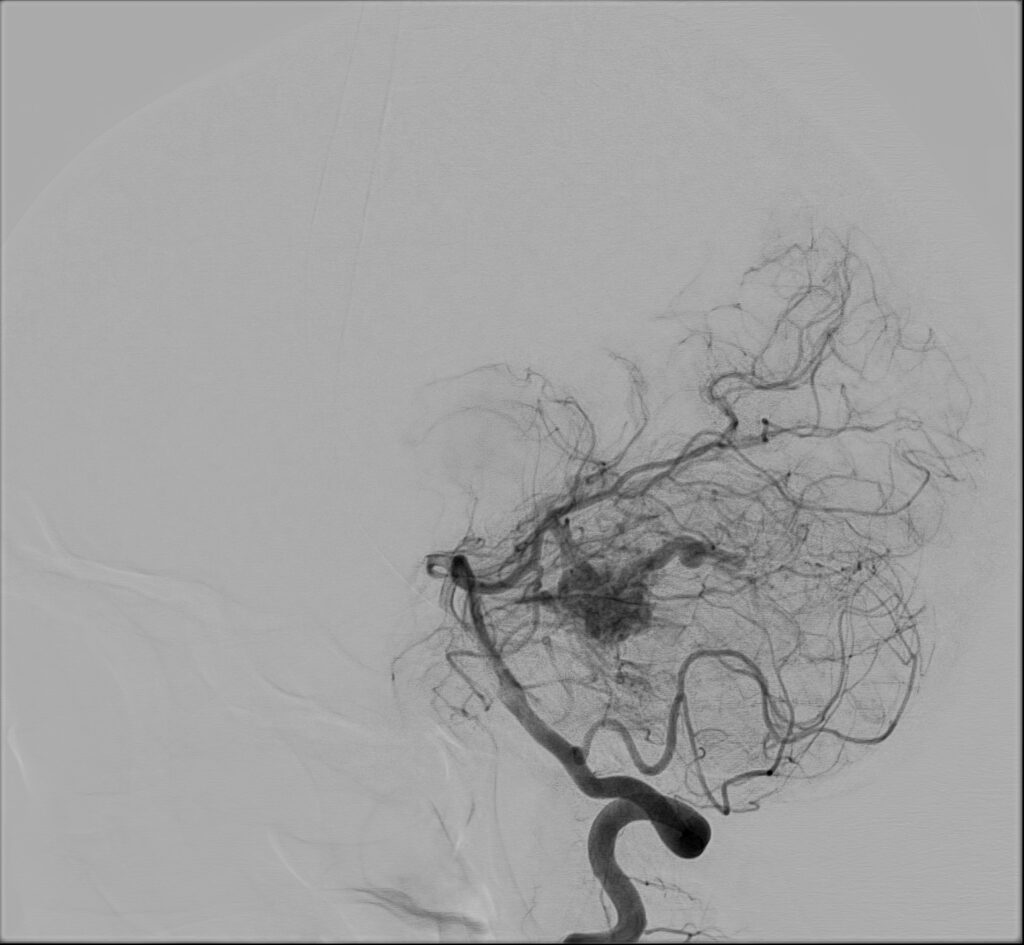

W badaniu CT widoczne jest rozległe krwawienie dokomorowe.

W badaniu angiografii subtrakcyjnej widoczne jest rozległe (ponad 3 cm) gniazdo naczyniowe zaopatrywane z tętnicy przedniej mózgu prawej, zarówno z gałęzi okołospoidołowej, która oddawała 2 tętnice żywiące, jak i gałęzi korowych, oddając jedno naczynie żylne drenujące do zatoki strzałkowej górnej.

W tym przypadku chora została zakwalifikowana do leczenia operacyjnego – kraniotomii czołowej przystrzałkowej i resekcji zmiany naczyniowej. Zmiana została usunięta, bez nowych deficytów neurologicznych. W kontrolnym badaniu DSA nie uwidoczniono resztkowej przetoki naczyniowej, co jest sukcesem operacyjnym.